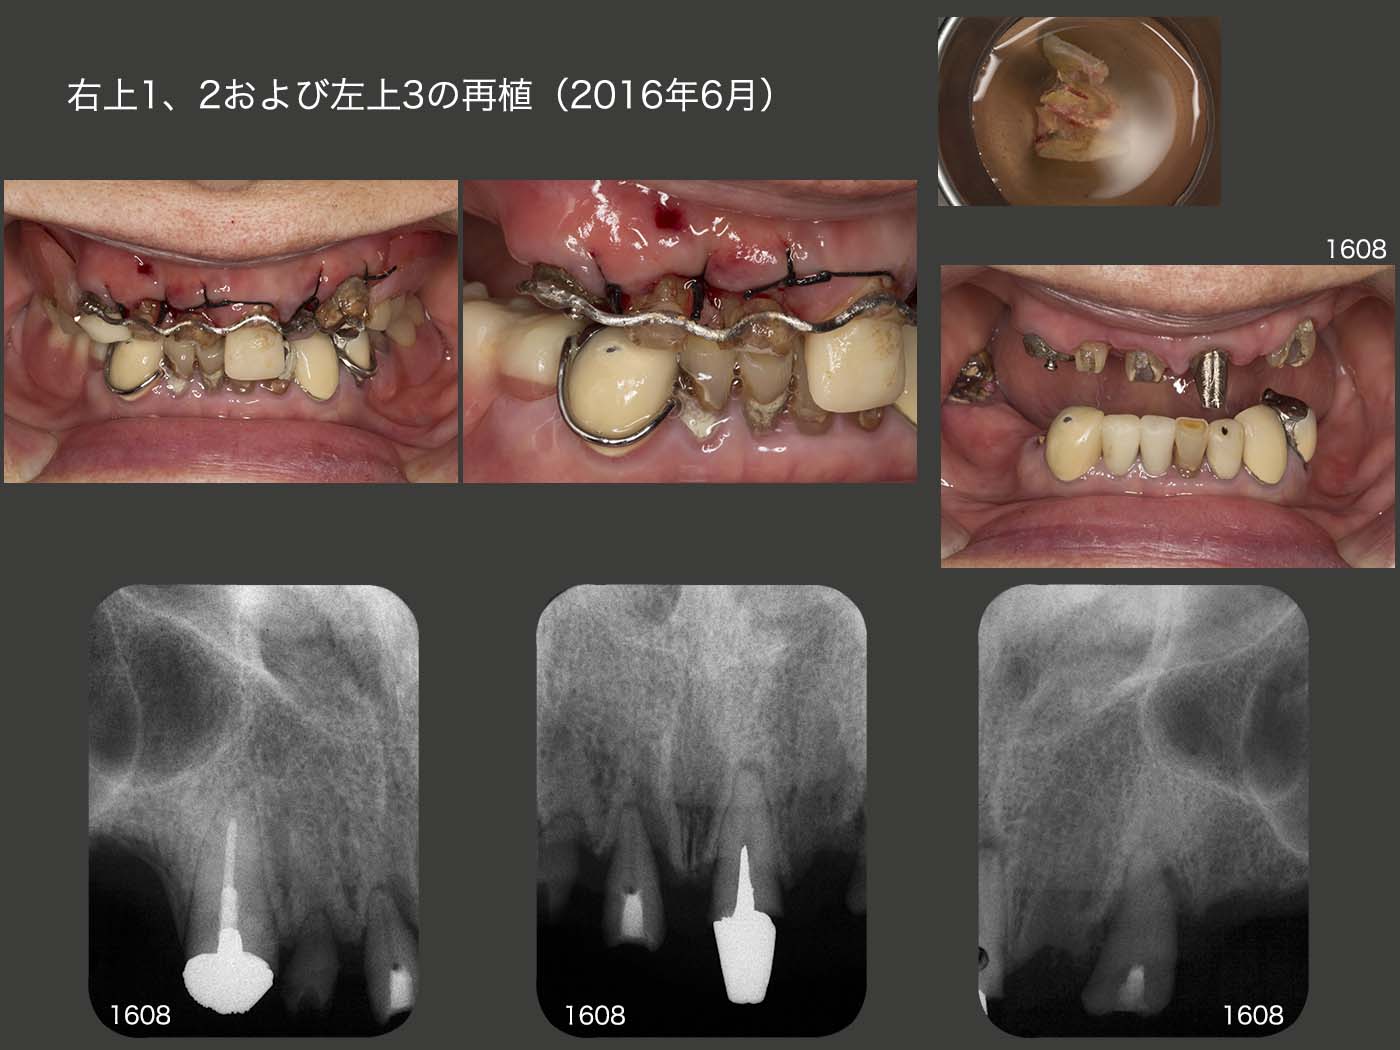

まず右上3の歯を足し、つぎに同歯の感染根管治療を行った。その後、暫間のOリングアタッチメントを装着し、義歯の維持を担ってもらった。なお、アタッチメント根面板の所に保持を設け、ワイヤーを固定できるように細工しておいた。 以上準備が整ったところで、2016年6月に右上3および左上1を固定源として、右上1、2および左上3の再植を同時に行った。この際、歯肉の上に健康な歯質が得られるところまで挺出し、ワイヤーに固定した。 デンタルX線写真は、術後2ヵ月半の状態であるが、右上2の動揺は収まらなかった。また左上3の遠心に7mmの歯周ポケットが残ったため、同部の歯肉切除を行った。